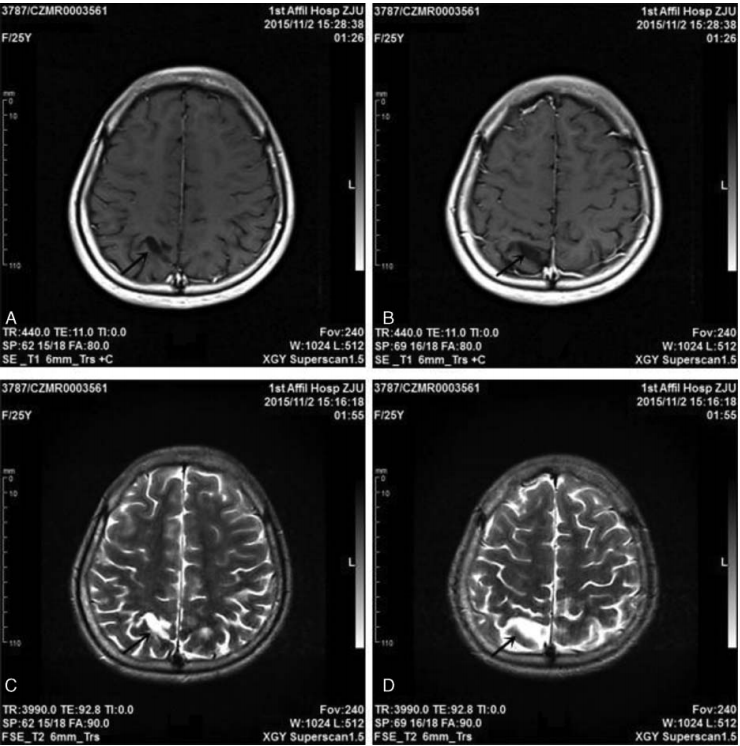

脑萎缩 右侧额叶局限性萎缩(硬膜下间隙增宽) 患者,男性,非aids, 病程